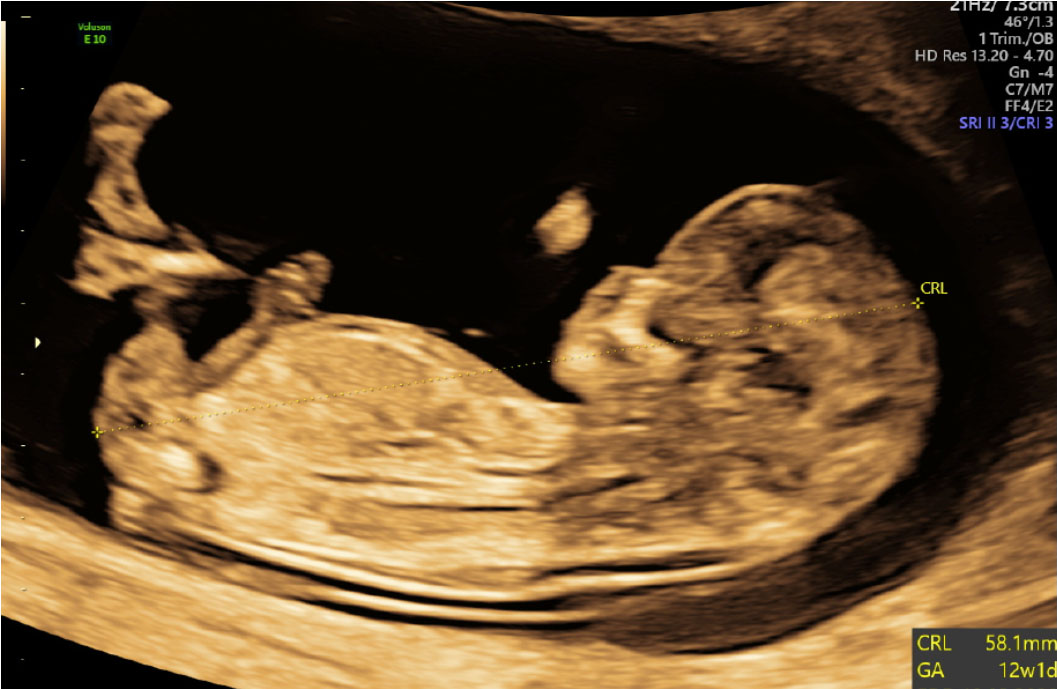

Foster uge 12+1, ultralyd

Ultralydskanning af tidlig intrauterin graviditet med crown rump længde (CRL) på 58 mm svarende til uge 12+1.